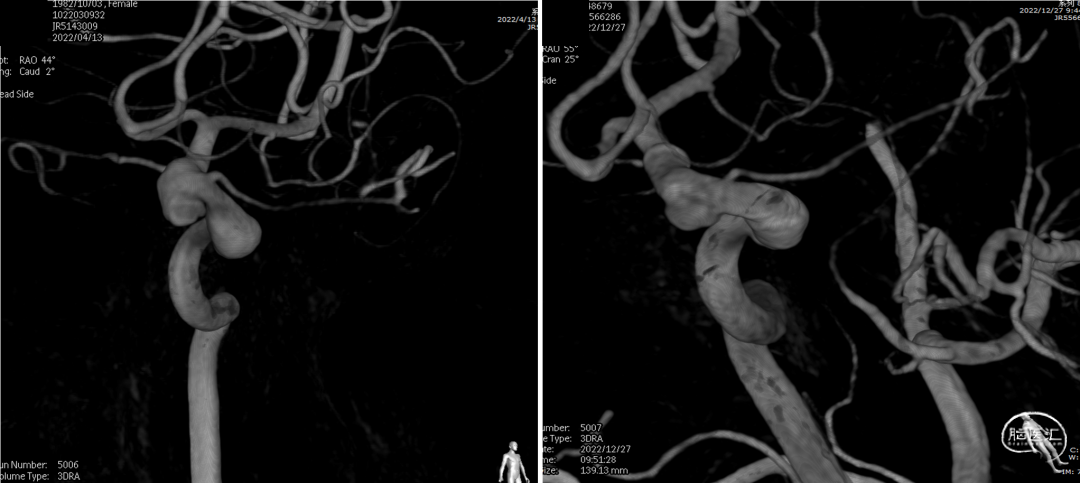

全脑血管造影(2022-04-13)

右颈内动脉3D重建(海绵窦段宽径7.2mm)

全脑血管造影

左颈内动脉3D重建图像(眼段宽径7.8mm)

左颈内动脉3D重建图像(海绵窦段宽径6.5mm)

术前、术后3D图像对比